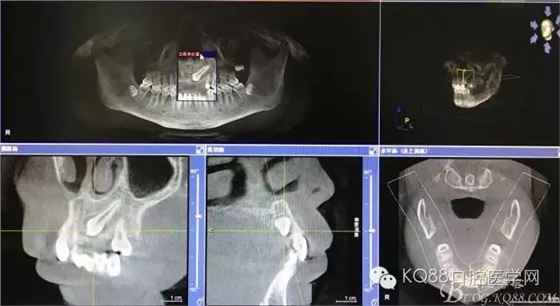

患者、王xx、男,17歲。主訴:牙齒排列不齊,要求治療。專(zhuān)科檢查:63乳牙滯留、22、23未萌出,cbct檢查:22牙冠畸形、過(guò)小牙,23高位埋伏阻生。正畸科治療計(jì)劃:拔除63、22,開(kāi)窗正畸牽引23。患者同意治療方案,簽知情同意書(shū),轉(zhuǎn)診外科,拔除63、22,并行23開(kāi)窗術(shù)+托槽粘接。

圖2.全景片影像檢查:23牙冠的遠(yuǎn)中還有一顆22畸形牙、及63滯留

圖3.冠向切面:23牙冠緊鄰21的牙根

圖4.縱剖面顯示23位于腭側(cè)

圖5.水平切面觀23位于腭側(cè)